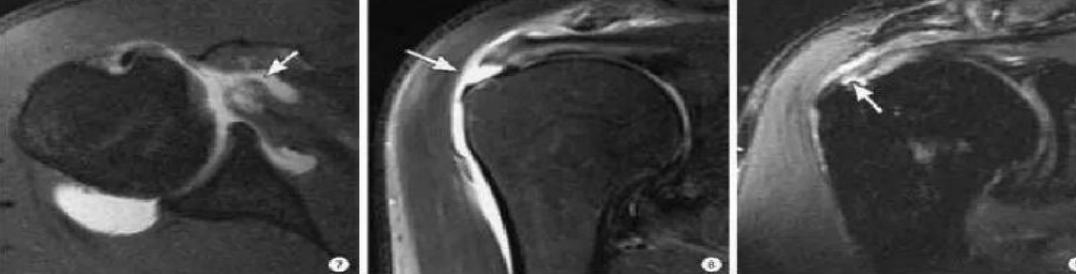

磁共振及磁共振关节造影:MRI是目前检查肩袖损伤最有效的影像学方法。MRI通过形态和信号的异常反应可显示肩袖损伤的各期表现。磁共振关节造影是在透视下经关节囊内注射含碘造影剂。由于关节囊的扩张,微小的肩袖撕裂在造影剂的衬托下显示得更为清楚,磁共振关节造影的准确率超过90%。

关节镜诊治:近期,关节镜的检查被认为是诊断肩袖部分撕裂的“金标准”,主要用于一些诊断较困难的病例。